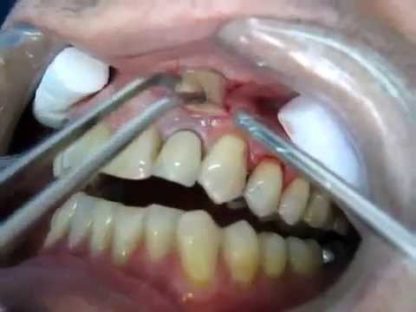

En este video se enseña como drenar un absceso. Para verlo si no sabes hacerlo o para simplemente recordar el procedimiento

Como drenar un absceso